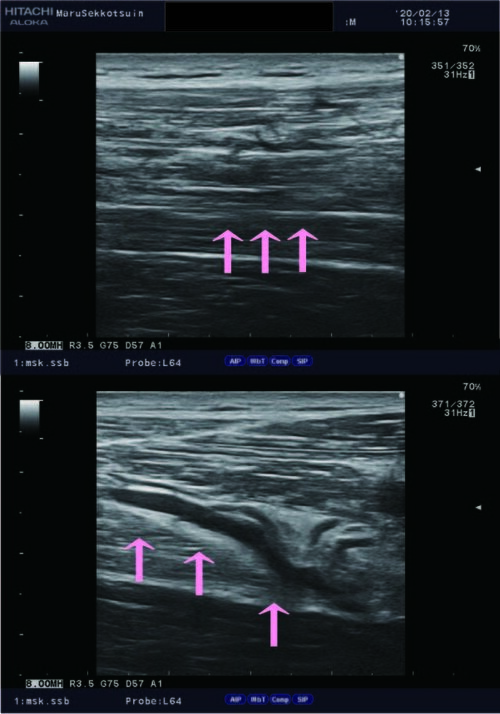

しっかり問診、視診、触診後、確認の為にエコー検査。

結果「ハムストリングス 半腱様筋の肉離れ」と判明。

肉離れ.jpg